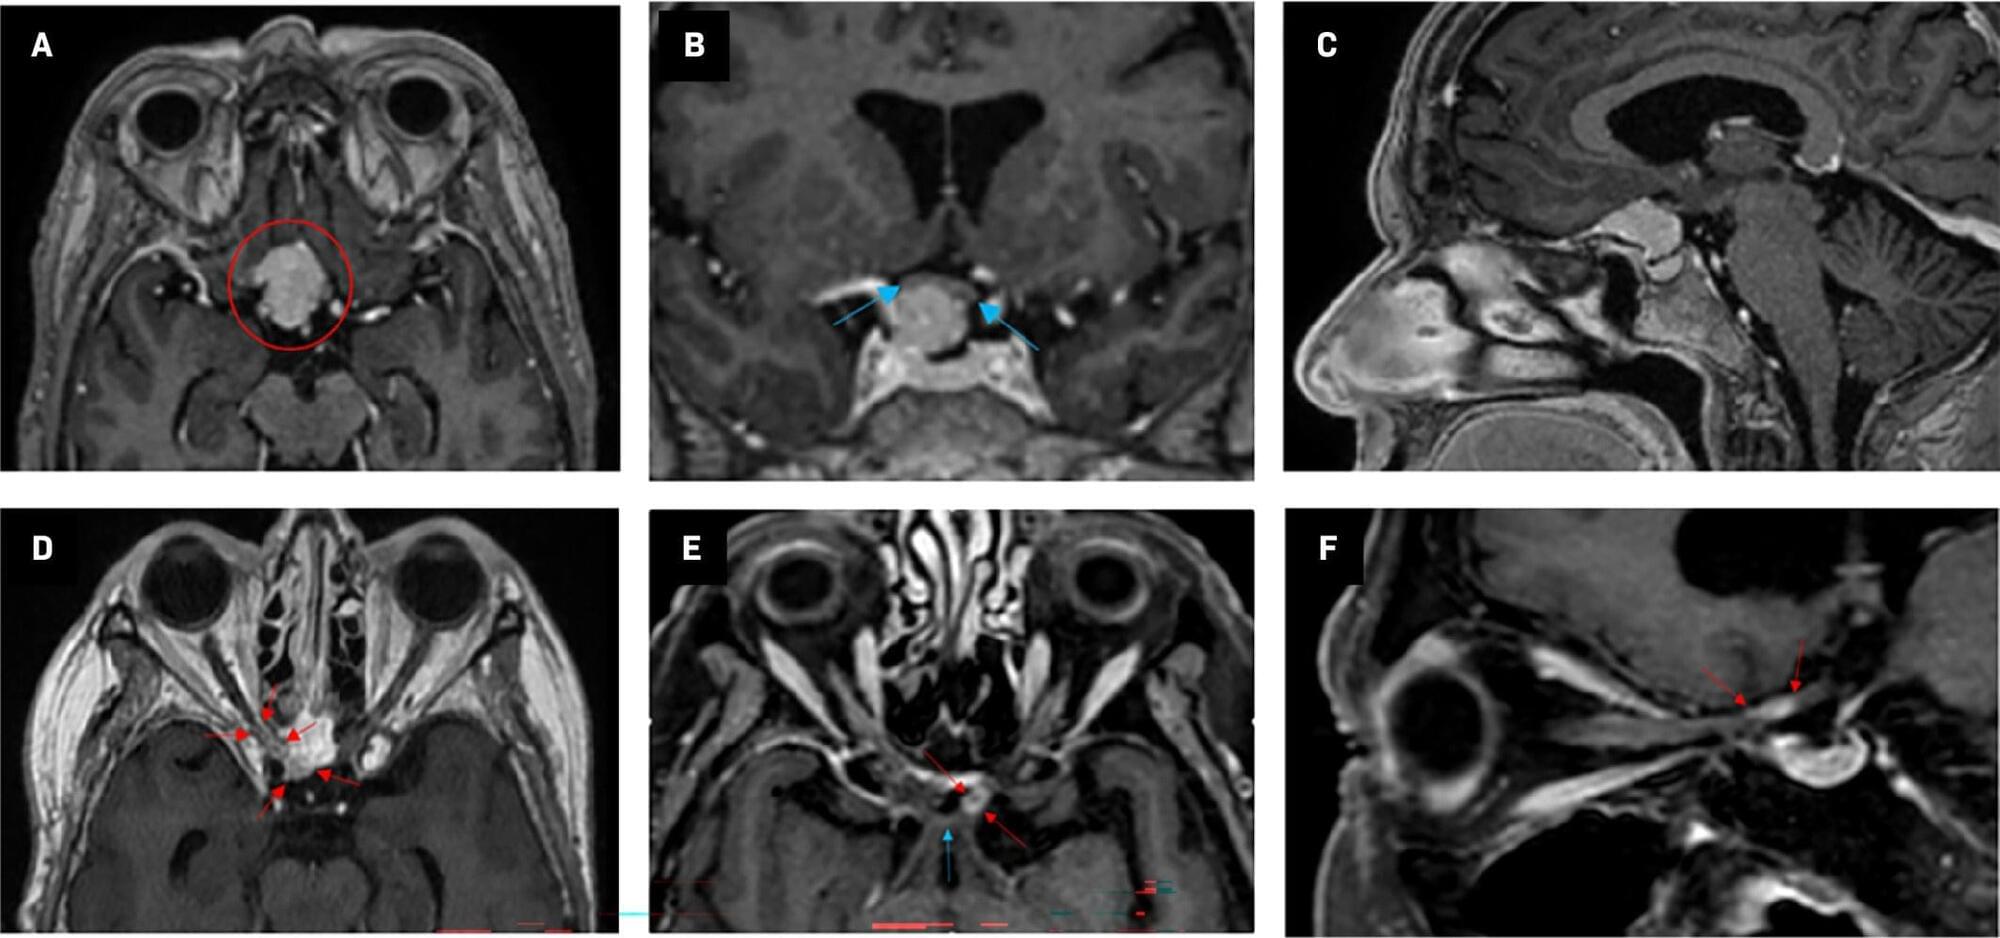

Based on recurrent disease, high probability of microscopic residual tumor remnants, and progressive loss of visual function, the patient was offered postoperative radiation therapy delivered with photons. Radiation therapy was administered 4 months following the last surgical procedure, and a conservative fractionation of 1.8 Gy in 29 fractions, with a total dose of 52.2 Gy, was chosen to keep anterior visual pathway doses below what is considered safe (Table 1) according to the European Particle Therapy Network Consensus. These standards recommend doses below 55 Gy to 0.03 cm3 (D 0.03cc) to the chiasm and the optic nerves.1 For the chiasm, the maximum dose (D max) was 53.7 Gy and the mean dose (D mean) was 51.7 Gy. The right optic nerve had a D max of 53.3 Gy and a D mean of 48.8 Gy, whereas the left optic nerve had a D max of 52.3 Gy and a D mean of 30.5 Gy. Radiation therapy dose distribution is shown in Figure 3. After radiation therapy, the patient reported minor improvement in visual function. Unfortunately, 7 to 8 months later her visual function again deteriorated over only a few weeks. Both eyes were affected, and deterioration was most pronounced in her left eye, with only finger counting possible and nearly total visual field loss. In the right eye, visual acuity was 20/60, with a substantially reduced visual field, especially in the lower 2 quadrants.

RION is primarily a diagnosis of exclusion, with tumor recurrence being the most important differential diagnosis. Tumor progression often results in a slower course of visual loss than RION.2 The patientâs vision loss was painless and rapid in onset, and radiological findings were bilateral and not consistent with neoplastic progression. Although MRI findings are nonspecific in RION-affected patients, neuro-ophthalmological examinations and clinical course/timing pointed to RION as the most likely cause of the patientâs visual loss. Systemic steroids in high doses were administered for 2 weeks before gradual tapering off, without any improvement in visual function. As a last effort to improve visual function, it was decided to try bevacizumab 7.5 mg/kg every 3 weeks. Treatment was well tolerated, with no reported side effects.